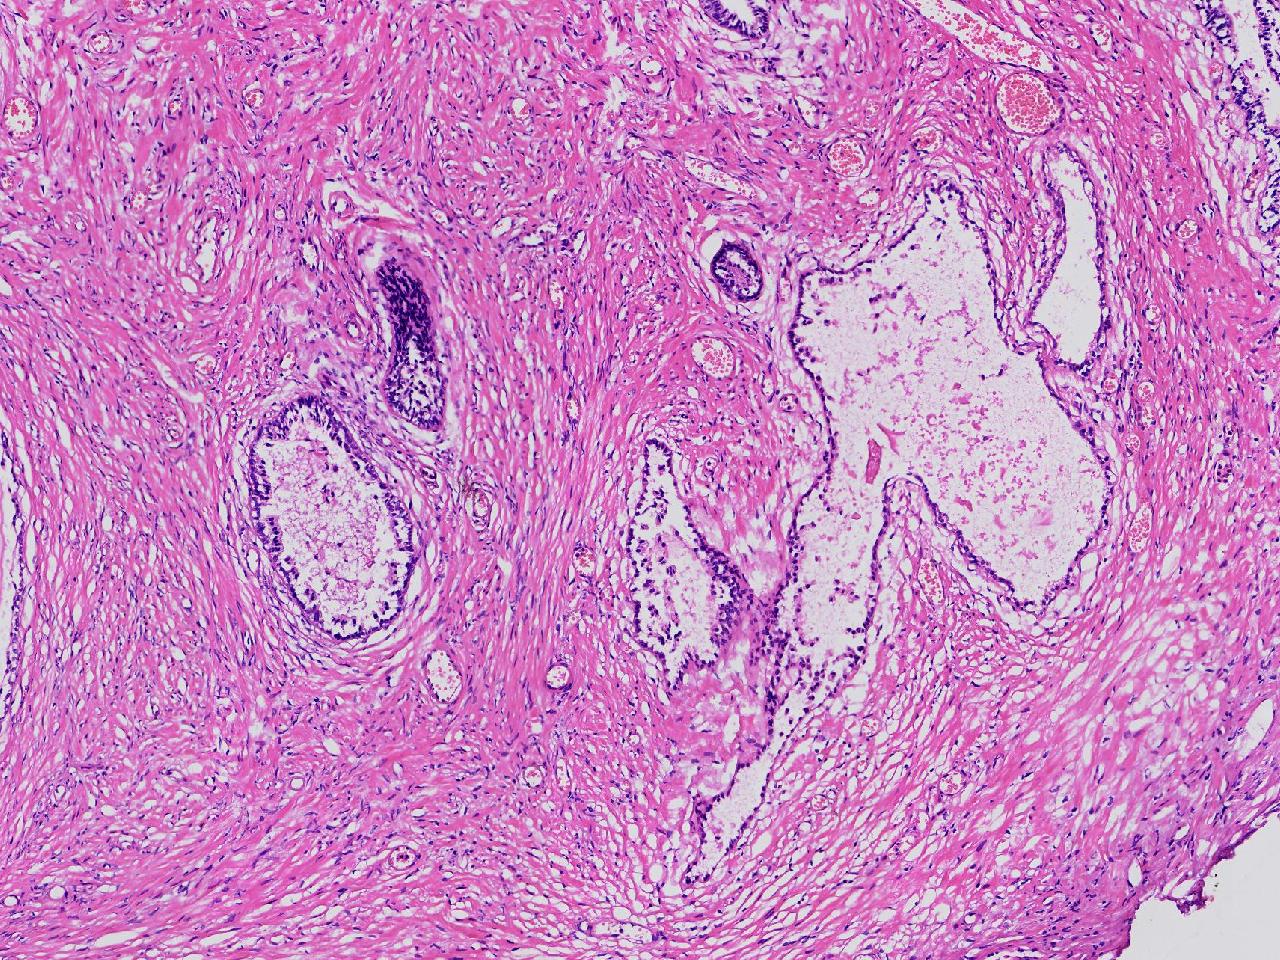

良性前列腺增生?

男,68岁,排尿困难半年余。行前列腺前切术。

前列腺电切标本

灰粉色条索状软组织多块,4X3X3厘米。

考虑为良性前列腺增生症

良性增生

BPH.